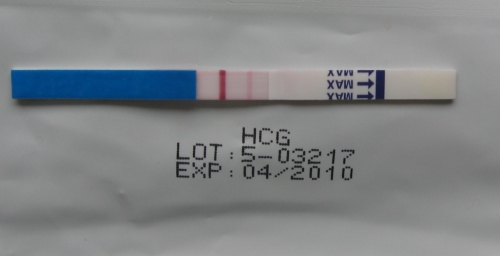

2008.03.24 14:07

2008.03.24 16:29

2008.03.24 23:21